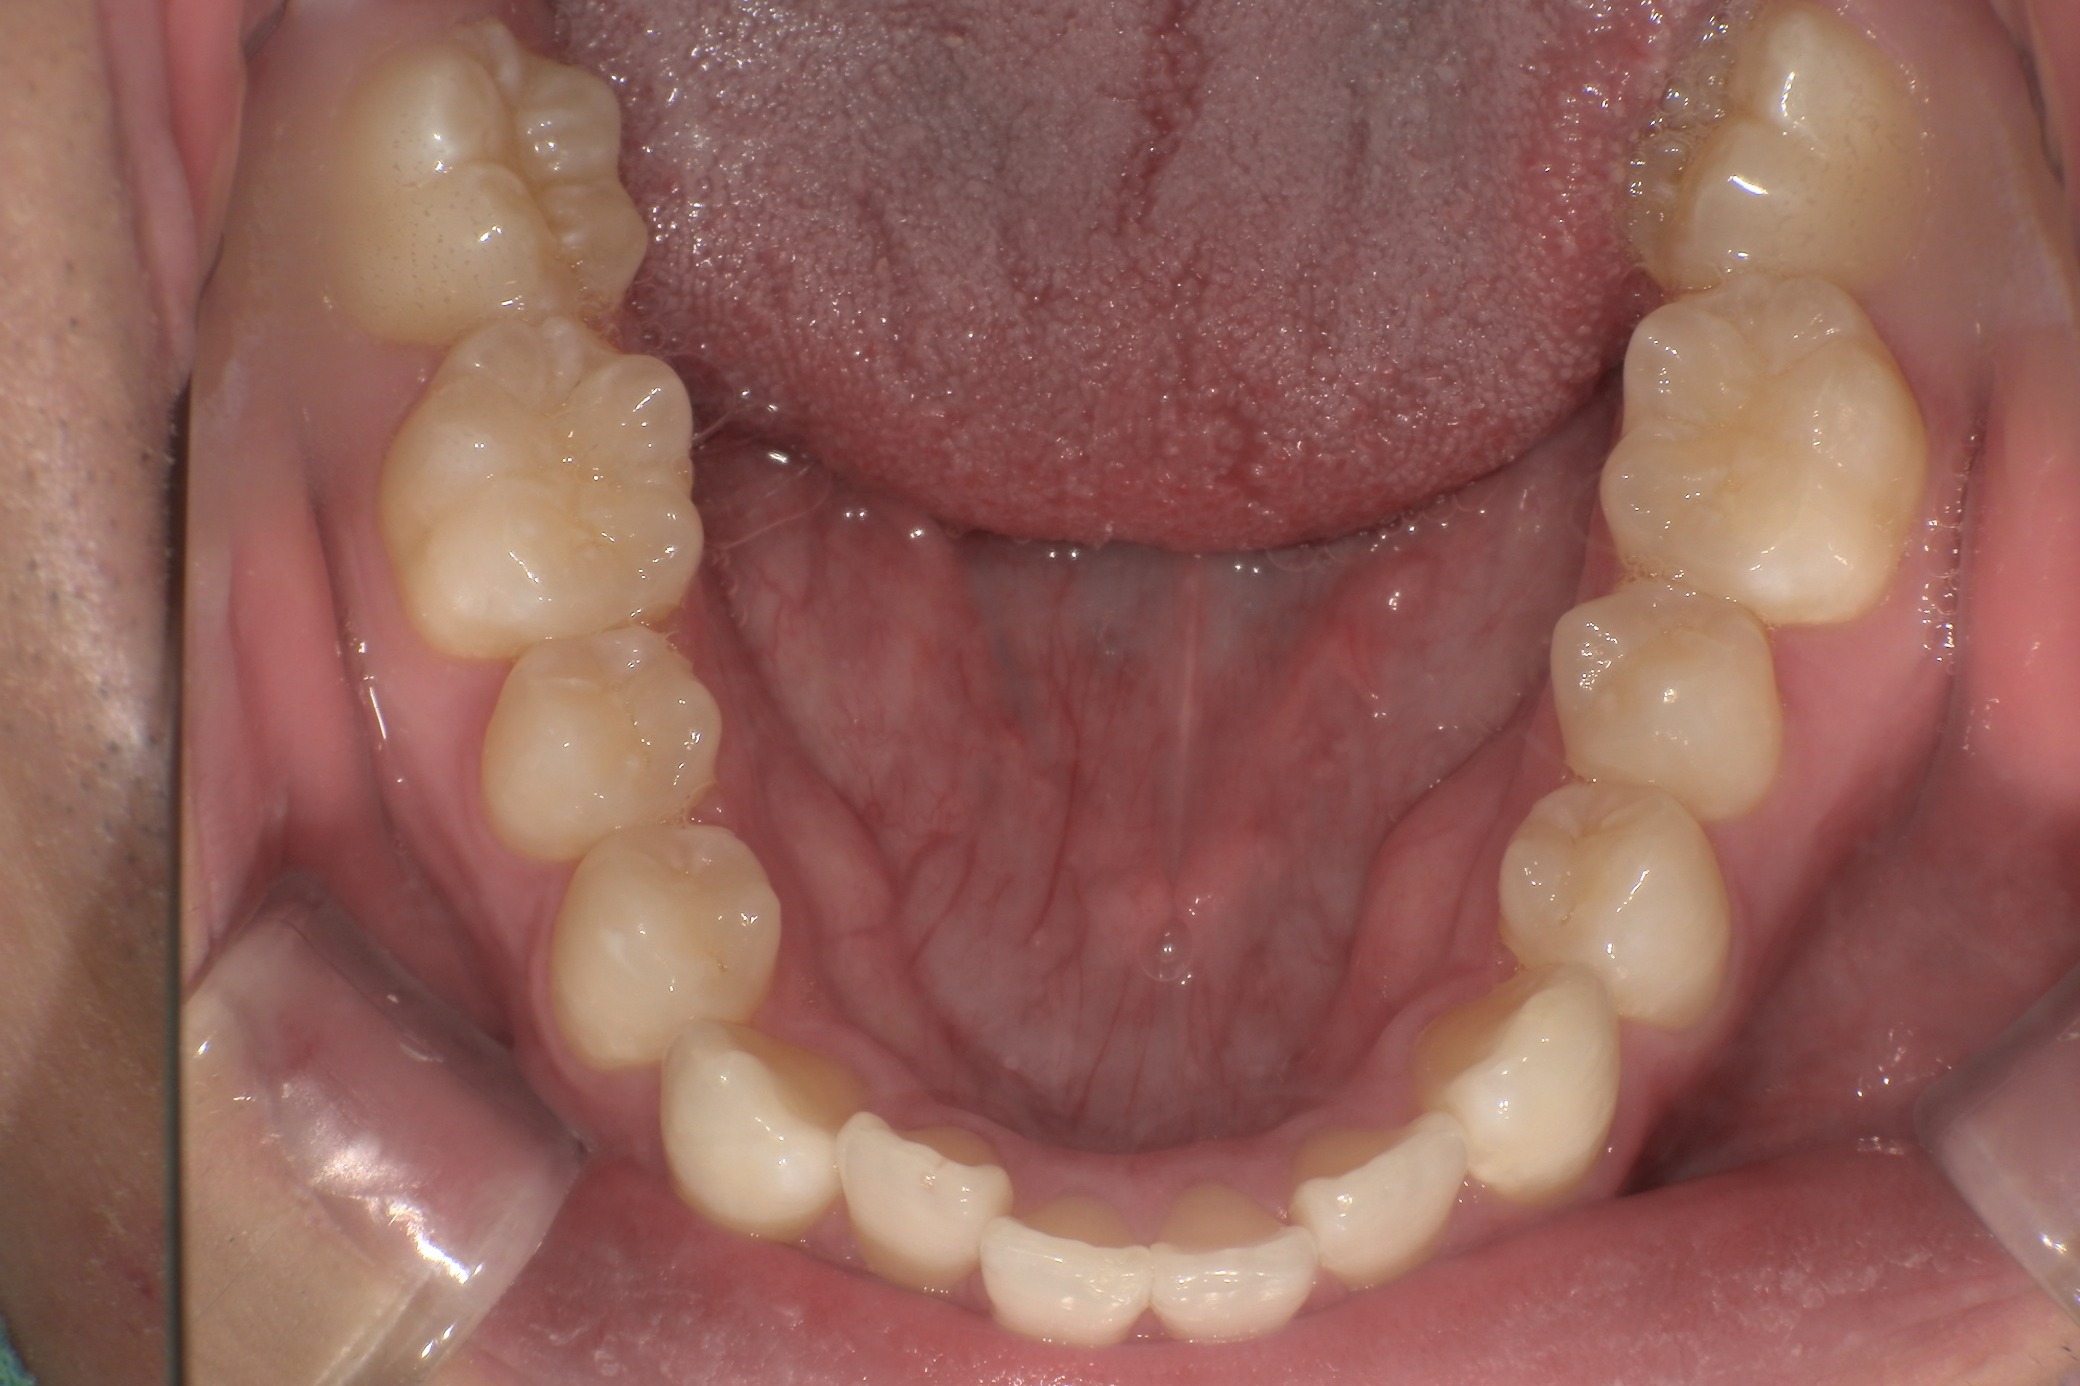

人と接する機会が多く、第一印象を大切にしたいと考え、写真写りや笑顔への自信を高めたいという思いから矯正を決意された矯正当時学生だった22歳男性の H.S.様に、スマイルモア矯正を選んだ理由を伺いました。

| 費用 | 360,000円(税込396,000円) |

| 治療期間 | 11ヶ月 |

| 治療内容 | マウスピースを用いた歯列矯正 |

| 追加処置 | IPR |

以前よりも歯並びが改善され、人とコミュニケーションをとることに自信がつきました。 「スマイルモア」という名前の通り、笑顔に自信がついたことで今までよりも口を開けて笑う機会も増えました。 矯正期間が年単位だったのですぐに変化があったわけではないですが、綺麗な仕上がりに満足しています。